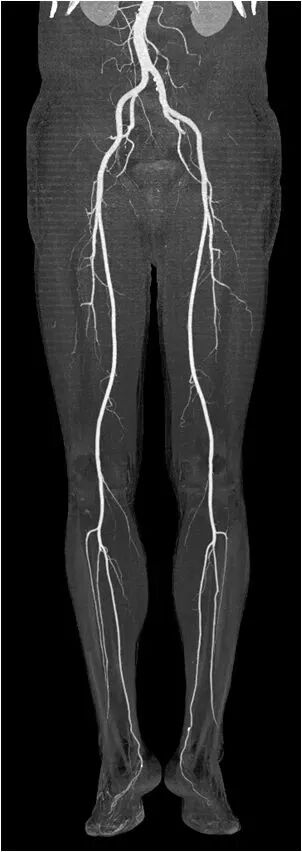

完成2米范围全身动脉扫描仅需3秒,即可得到清晰图像。

全新0兆球管可持续行大范围扫描,轻松应对双下肢动脉CTA检查。